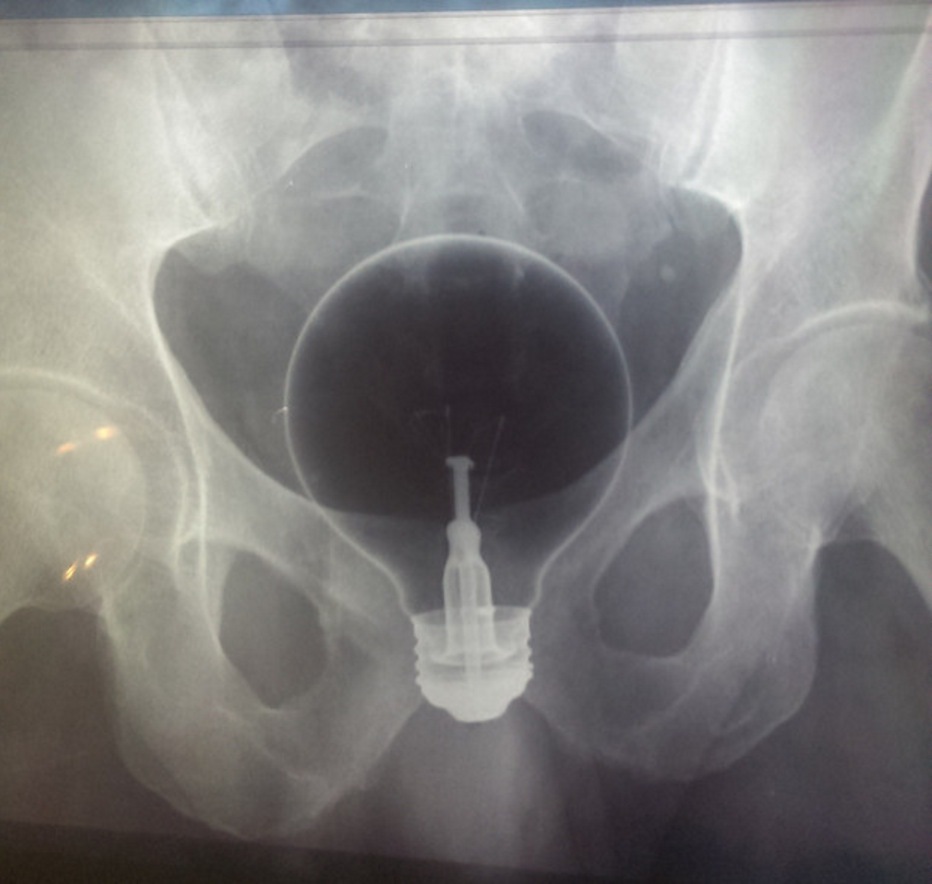

7. A light bulb

"My mother will always remember the guy who put a light bulb up his butt."